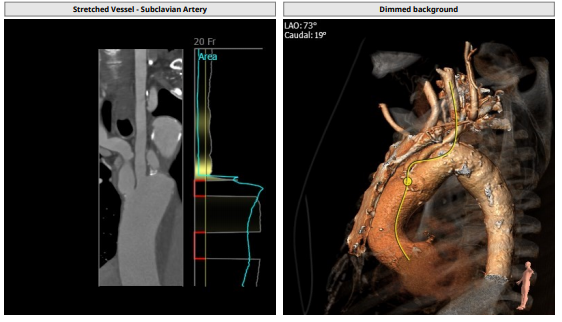

病例难度主要在于患者入路,该患者腹主迂曲且腹主动脉瘤,无法经常规股动脉入路进行植入,广东省医TAVR团队是国内率先开展颈动脉入路的中心之一,李捷教授介绍,经颈动脉入路TAVR的难点在于整个MDT团队的配合,对于手术器械的摆放,术中无菌操作,尤其是释放瓣膜时器械的整体稳定性相比于常规股动脉入路都对整个团队提出更高的要求。此例患者心功能差,且为避免长时间阻断颈动脉对患者远期脑功能造成影响,导管操作时间需尽量控制在20分钟以内,此次此颈入路反流病例,在华南地区,尚属首例。

入路解剖: